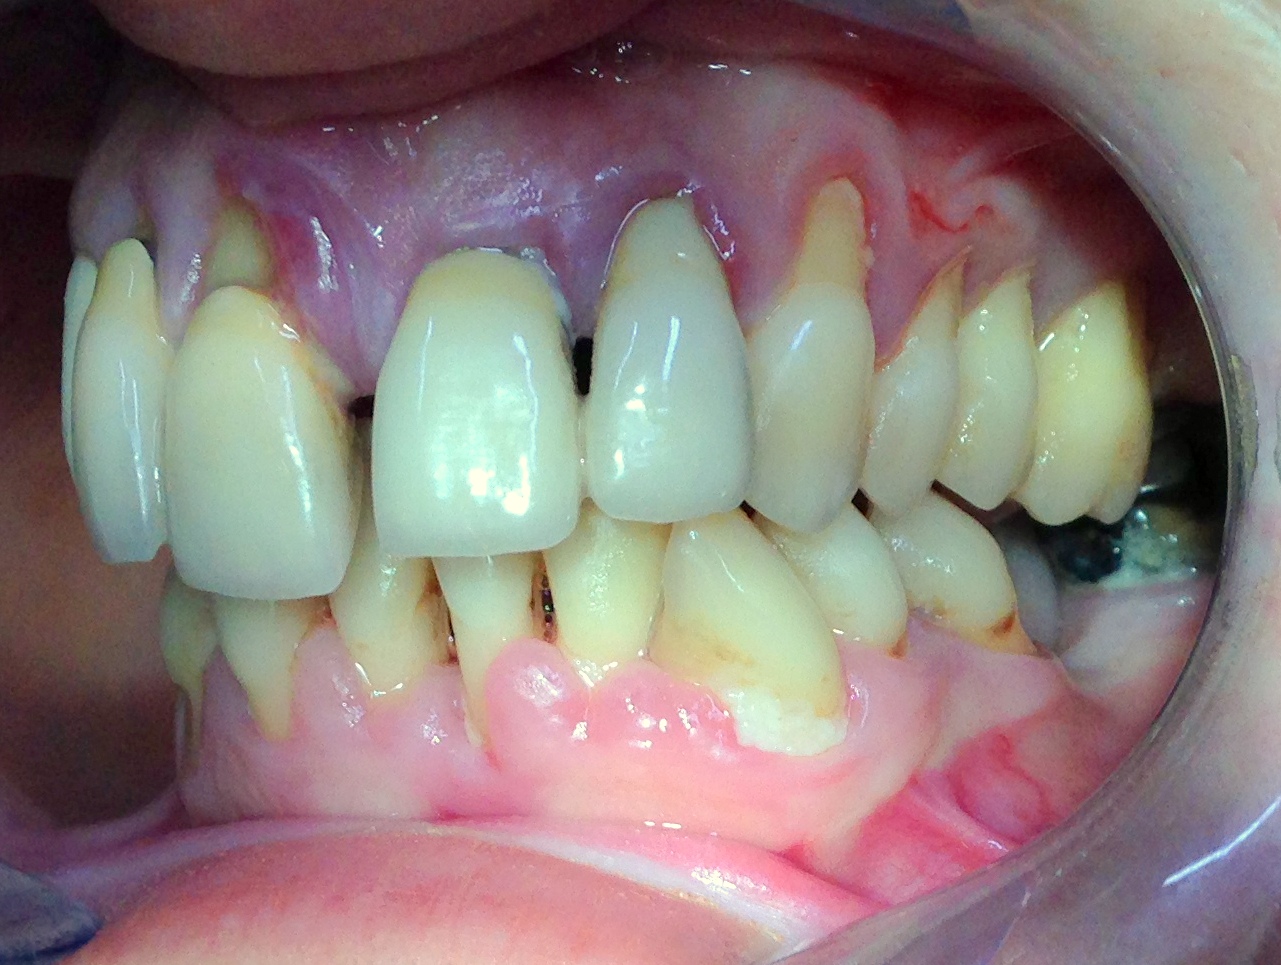

La paziente di 45 anni si è presentata alla nostra attenzione con il desiderio di risolvere la problematica estetica del gruppo frontale.

L'esame clinico ha evidenziato uno stato parodontale compromesso con migrazione vestibolare degli incisivi centrali e laterali.

Per prima cosa si è eseguita un'accurata terapia causale partendo da una seduta di igiene orale e da 4 sedute di levigatura radicolare. La paziente è stata istruita e motivata al mantenimento di una scrupolosa igiene domiciliare.